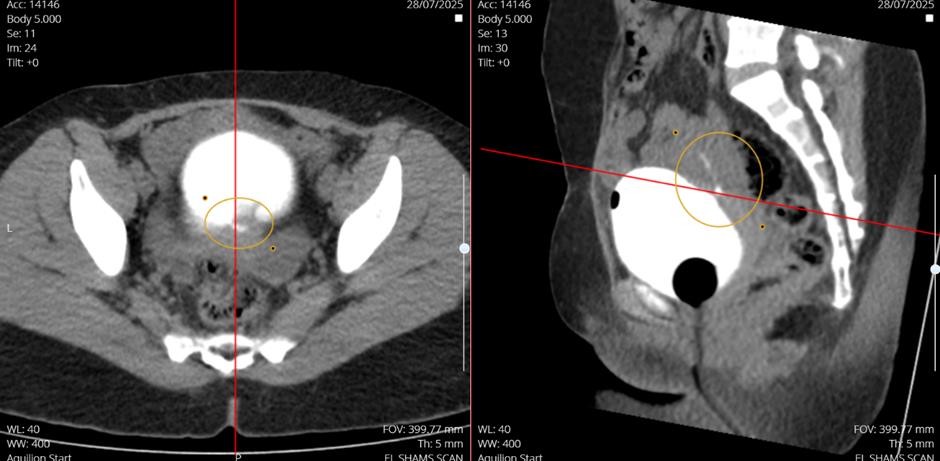

Findings: the imaging revealed a narrow fistulous connection between the posterior-superior surface of the urinary bladder and the overlying anterior uterine wall. Hyperattenuating water soluble contrast material was visualized extending from the bladder lumen to the uterine cavity (annotated axial and sagittal images).

• Incidental Finding: A left adnexal cyst measuring 47x28x44mm was identified.

• Diagnosis: Vesicouterine Fistula (Youssef’s syndrome).

Figure 01: Posterior-Superior surface of the urinary bladderand the overlying anterior uterine wall